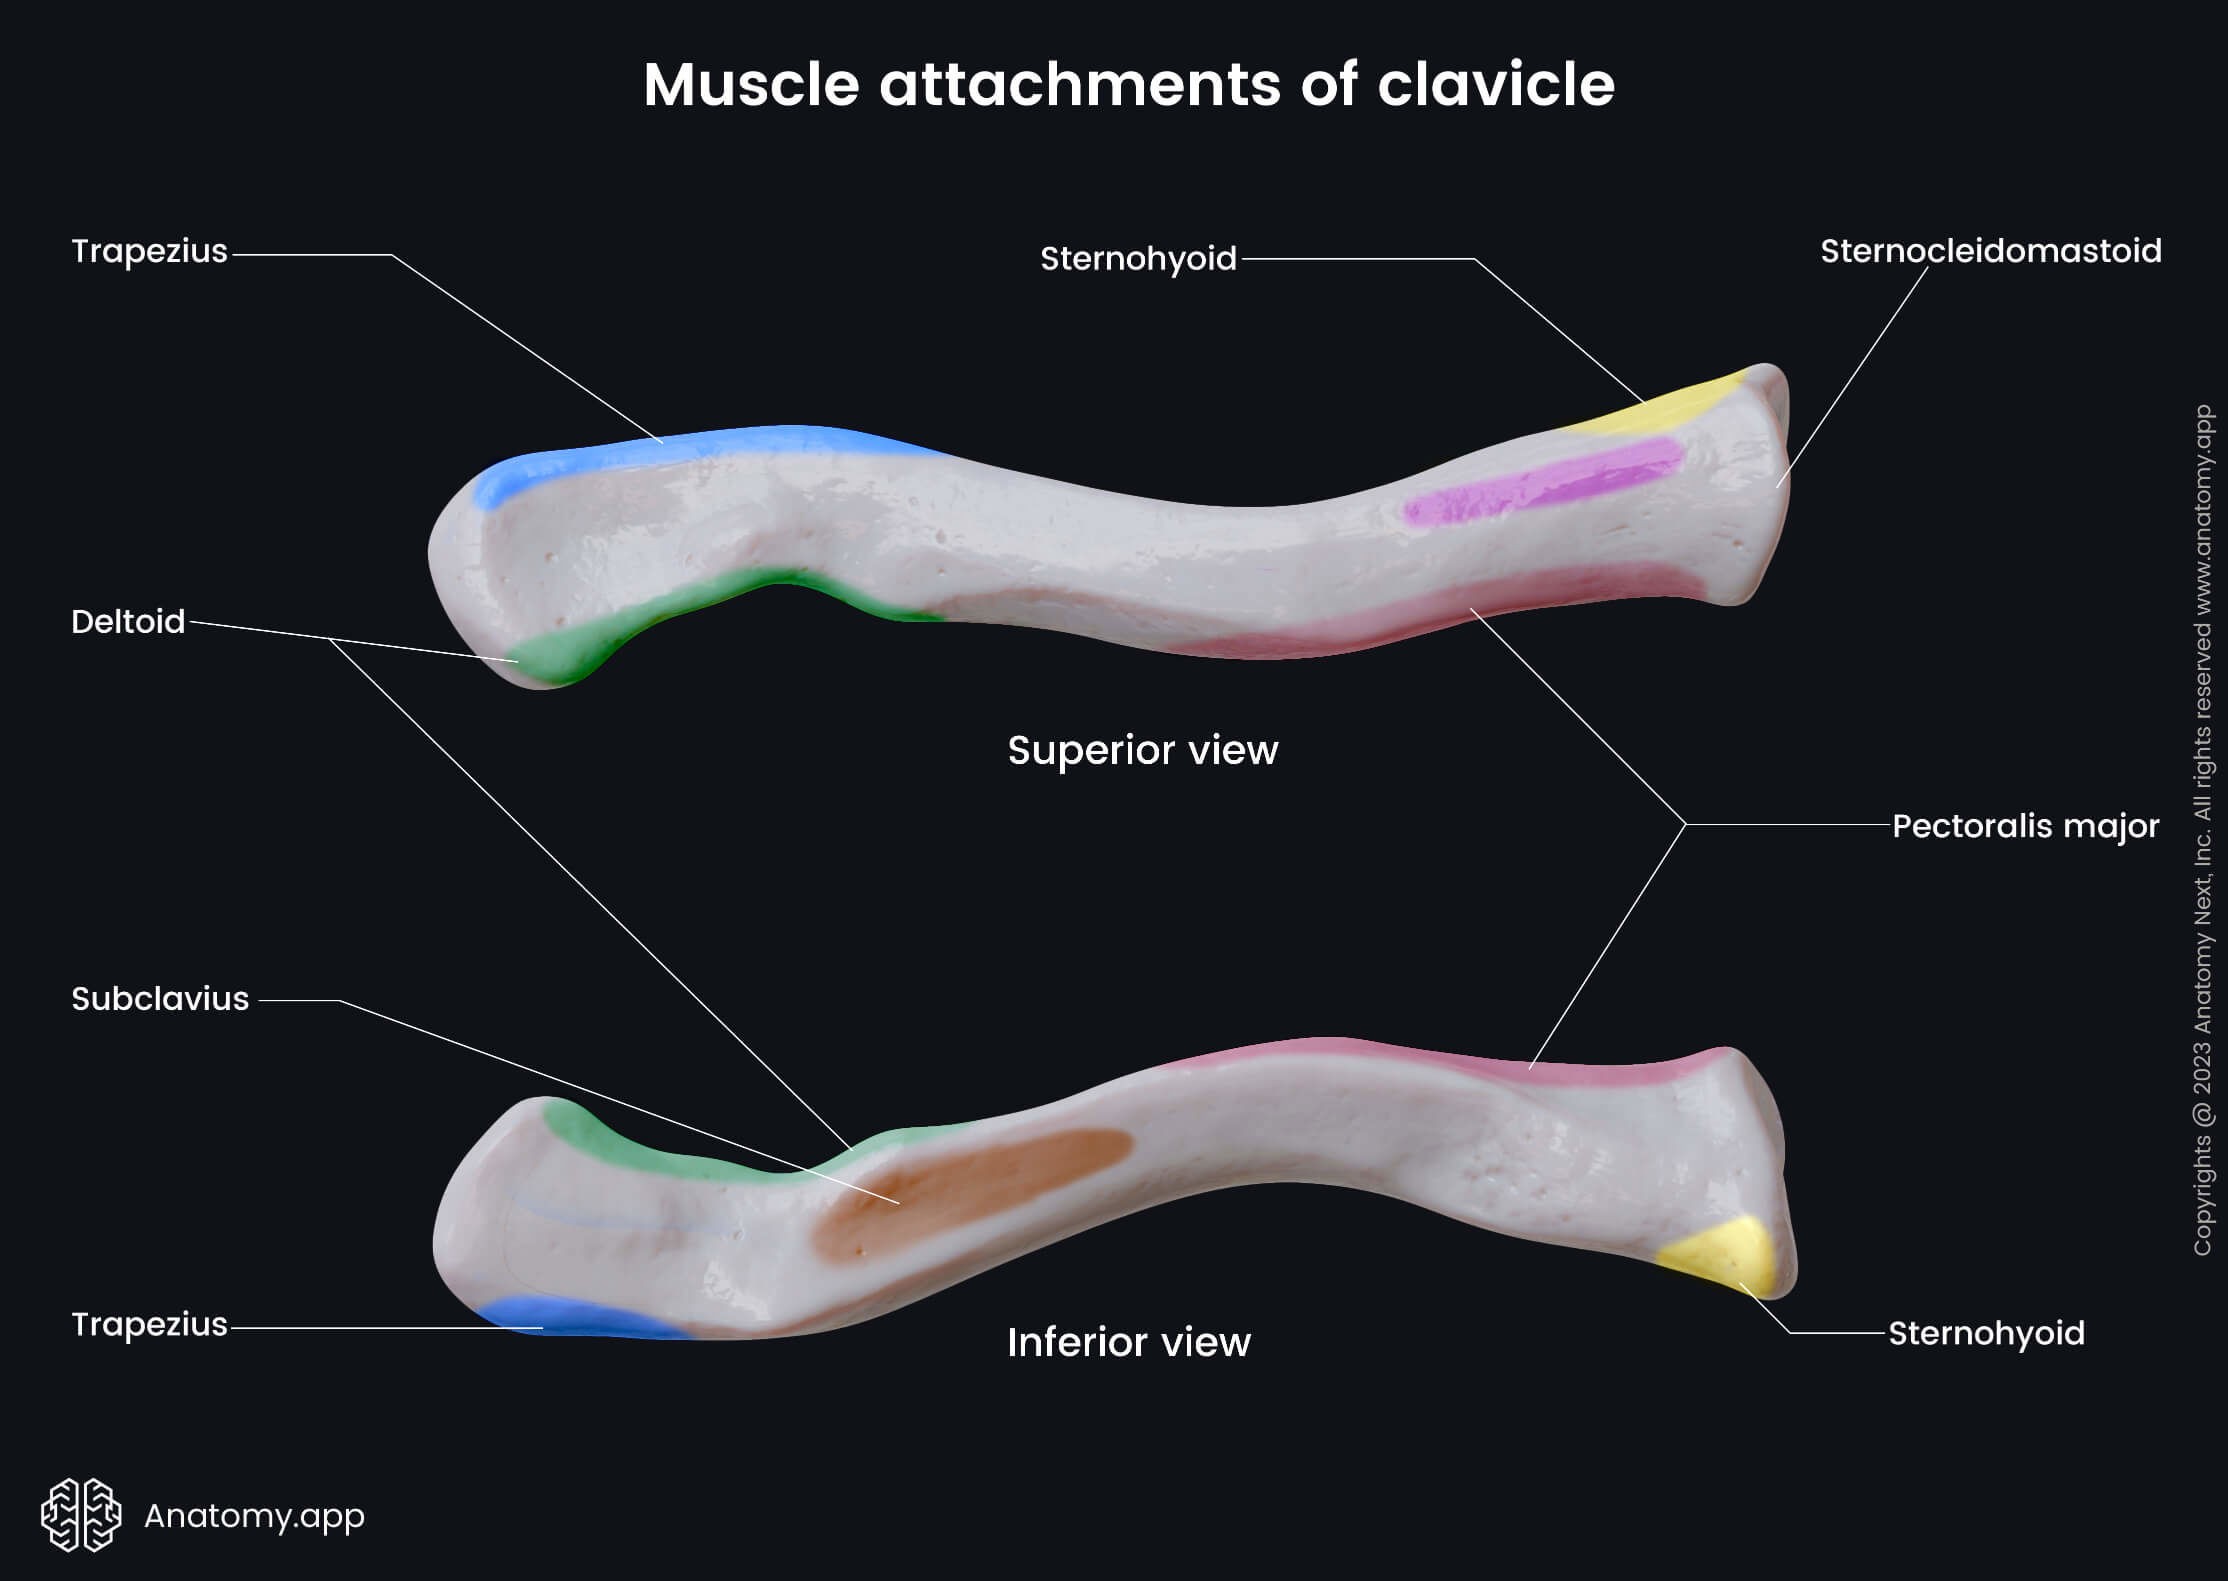

It acts as a strut that holds the shoulder away from the chest and allows free arm movement.

The clavicle lies above important nerves and blood vessels, which are carefully assessed in cases of fracture.